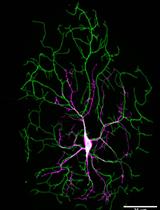

Optogenetics is the ideal tool for this purpose as it allows highly precise spatial and temporal regulation of proteins in vivo simply by exposure of the organism to light of a specific wavelength (Moglich and Moffat, 2010; Fenno et al., 2011). We have applied this approach to a variety of problems including embryonic development and homeostasis (Kaur et al., 2017; Bunnag et al., 2020), and have recently shown that inducing aggregation of soluble Aβ protein using optogenetics led to metabolic and physical damage and deteriorating lifespan and healthspan in 3 model organisms–Drosophila melanogaster, C. elegans and D. rerio, as well as in standard tissue culture models (Lim and Mathuru, 2017; Lim et al., 2020). Here, we describe the method used to construct an optogenetic light-inducible Aβ protein that oligomerizes on exposure to blue light in vivo in different model organisms and investigate the downstream detrimental effects using various metabolic assays and time-lapse live imaging. We used the photolyase homology region of the Arabidopsis thaliana cryptochrome 2 as an optogenetic switch (CRY2) protein that oligomerizes into photobodies quickly and reversibly in the presence of blue light (Mas et al., 2000; Bugaj et al., 2013). This CRY2 domain was generated as a Aβ-CRY2-mCherry fusion protein to induce aggregation of Aβ protein upon activation by blue light with visualization through the mCherry fluorescent protein.

Incorporation of this versatile tool with easily manipulatable genetic models such as D. melanogaster, C. elegans and D. rerio, gave us temporal control over the induction of soluble Aβ oligomers not feasible with other currently available Alzheimer’s animal models. We were also able to dissect the pathological effects of Aβ oligomers on embryos during development in real-time using live imaging as well as in adult flies (Lim et al., 2020). This model also allows us to generate mosaics of embryos such that only one half of the embryo, or a small portion is exposed to blue light. Hence, we can investigate the effects of targeted light-induced Aβ oligomerization on various anatomical structures such as the nervous system with the unlit portion of the embryo acting as the control. Functionality in both the invertebrate and vertebrate lab models demonstrates this technique’s application to study the biochemistry, metabolism, cellular and neuronal biology of induced Aβ oligomerization. The effects of potential drug interventions on lifespan, health span and metabolism can also be studied with this robust optogenetic approach in various model organisms. We were able to adopt different strategies to express the same transgene in both invertebrates and vertebrates, which should translate to mouse studies through the conditional knock-in approach. Aggregation could be induced in brains of adult mice with exposure to blue light to study the effects of Aβ-CRY2-mCh aggregation on neuronal function and behavior. This protocol is specific to Aβ, but could easily be adapted to other aggregating proteins simply by changing the starting gene.